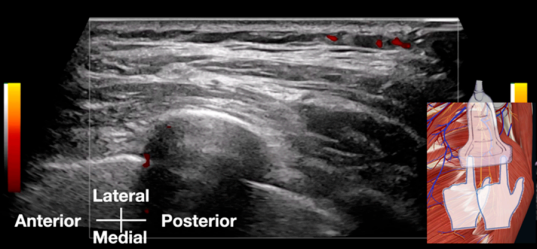

초음파로 '눈으로 보면서'신경을 눌러보고통증과 일치하는 진짜 원인을 찾아냅니다. 이 2025년 논문에서 주목할 점은 진단 방식입니다.

Sonoguided digital palpation (SDP) 이라는

기술을 썼는데요.

그냥 초음파로 보기만 하는 게 아니라,

초음파 프로브(탐촉자)로

환자의 통증 부위와 그 주변을

실시간으로 보면서 '직접' 눌러보는 겁니다.

https://doi.org/10.3390/diagnostics15151891

"여기가 아프세요?" 하고 눌렀을 때,

환자가 "아! 바로 거기예요!"

하는 통증(concordant pain)이 재현되고,

화면에서 문제가 되는 '장흉신경'의 위치를

정확하게 파악할 수 있게 되는거죠.